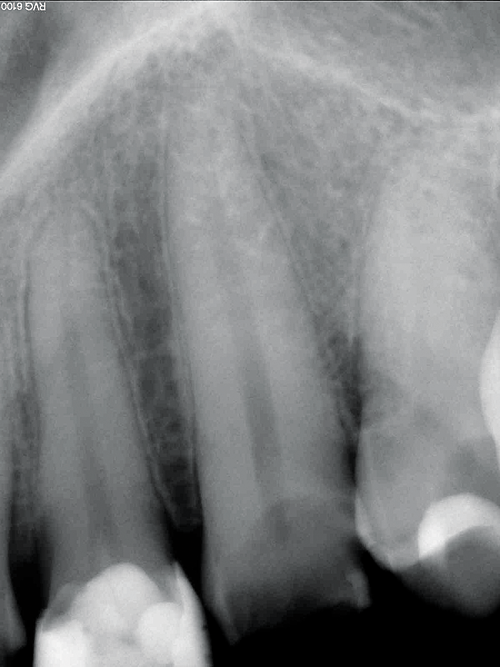

This clinical case demonstrates the use of CORE-FLO DC LITE with Bisco’s dual-cured UNIVERSAL PRIMER for post and core build-ups. The patient presented with advanced decay in multiple teeth. He was a relatively healthy 30-year-old male with a history of drug and alcohol abuse. He had recently completed a substance abuse rehabilitation program and wanted to finish his dental treatment.

He stopped his prior dental treatment while still in his temporary restorations. He eventually lost the temporaries and went without for several years. As a result he was left with extensive decay in the previously prepared anterior teeth (Figs. 1, 3).